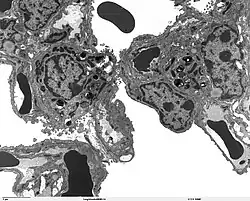

The protein encoded by this gene (SP-A2) is primarily synthesized in lung alveolar type II cells, as part of a complex of lipids and proteins known as pulmonary surfactant. The function of this complex is to reduce surface tension in the alveolus and prevent collapse during expiration. The protein component of surfactant helps in the modulation of the innate immune response, and inflammatory processes.[7]

The lung is the main site of SFTPA2 synthesis, but SFTPA2 mRNA expression has also been detected in the trachea, prostate, pancreas, thymus, colon, eye, salivary gland and other tissues. While the majority of these tissues express both SFTPA2 and SFTPA1 transcripts, only SFTPA2 expression was found in the trachea and prostate.[15] Using specific monoclonal antibodies for Surfactant protein A, the protein can be detected in lung alveolar type II pneumocytes, Club cells, and alveolar macrophages, but no extrapulmonary SP-A immunoreactivity was observed.[15]